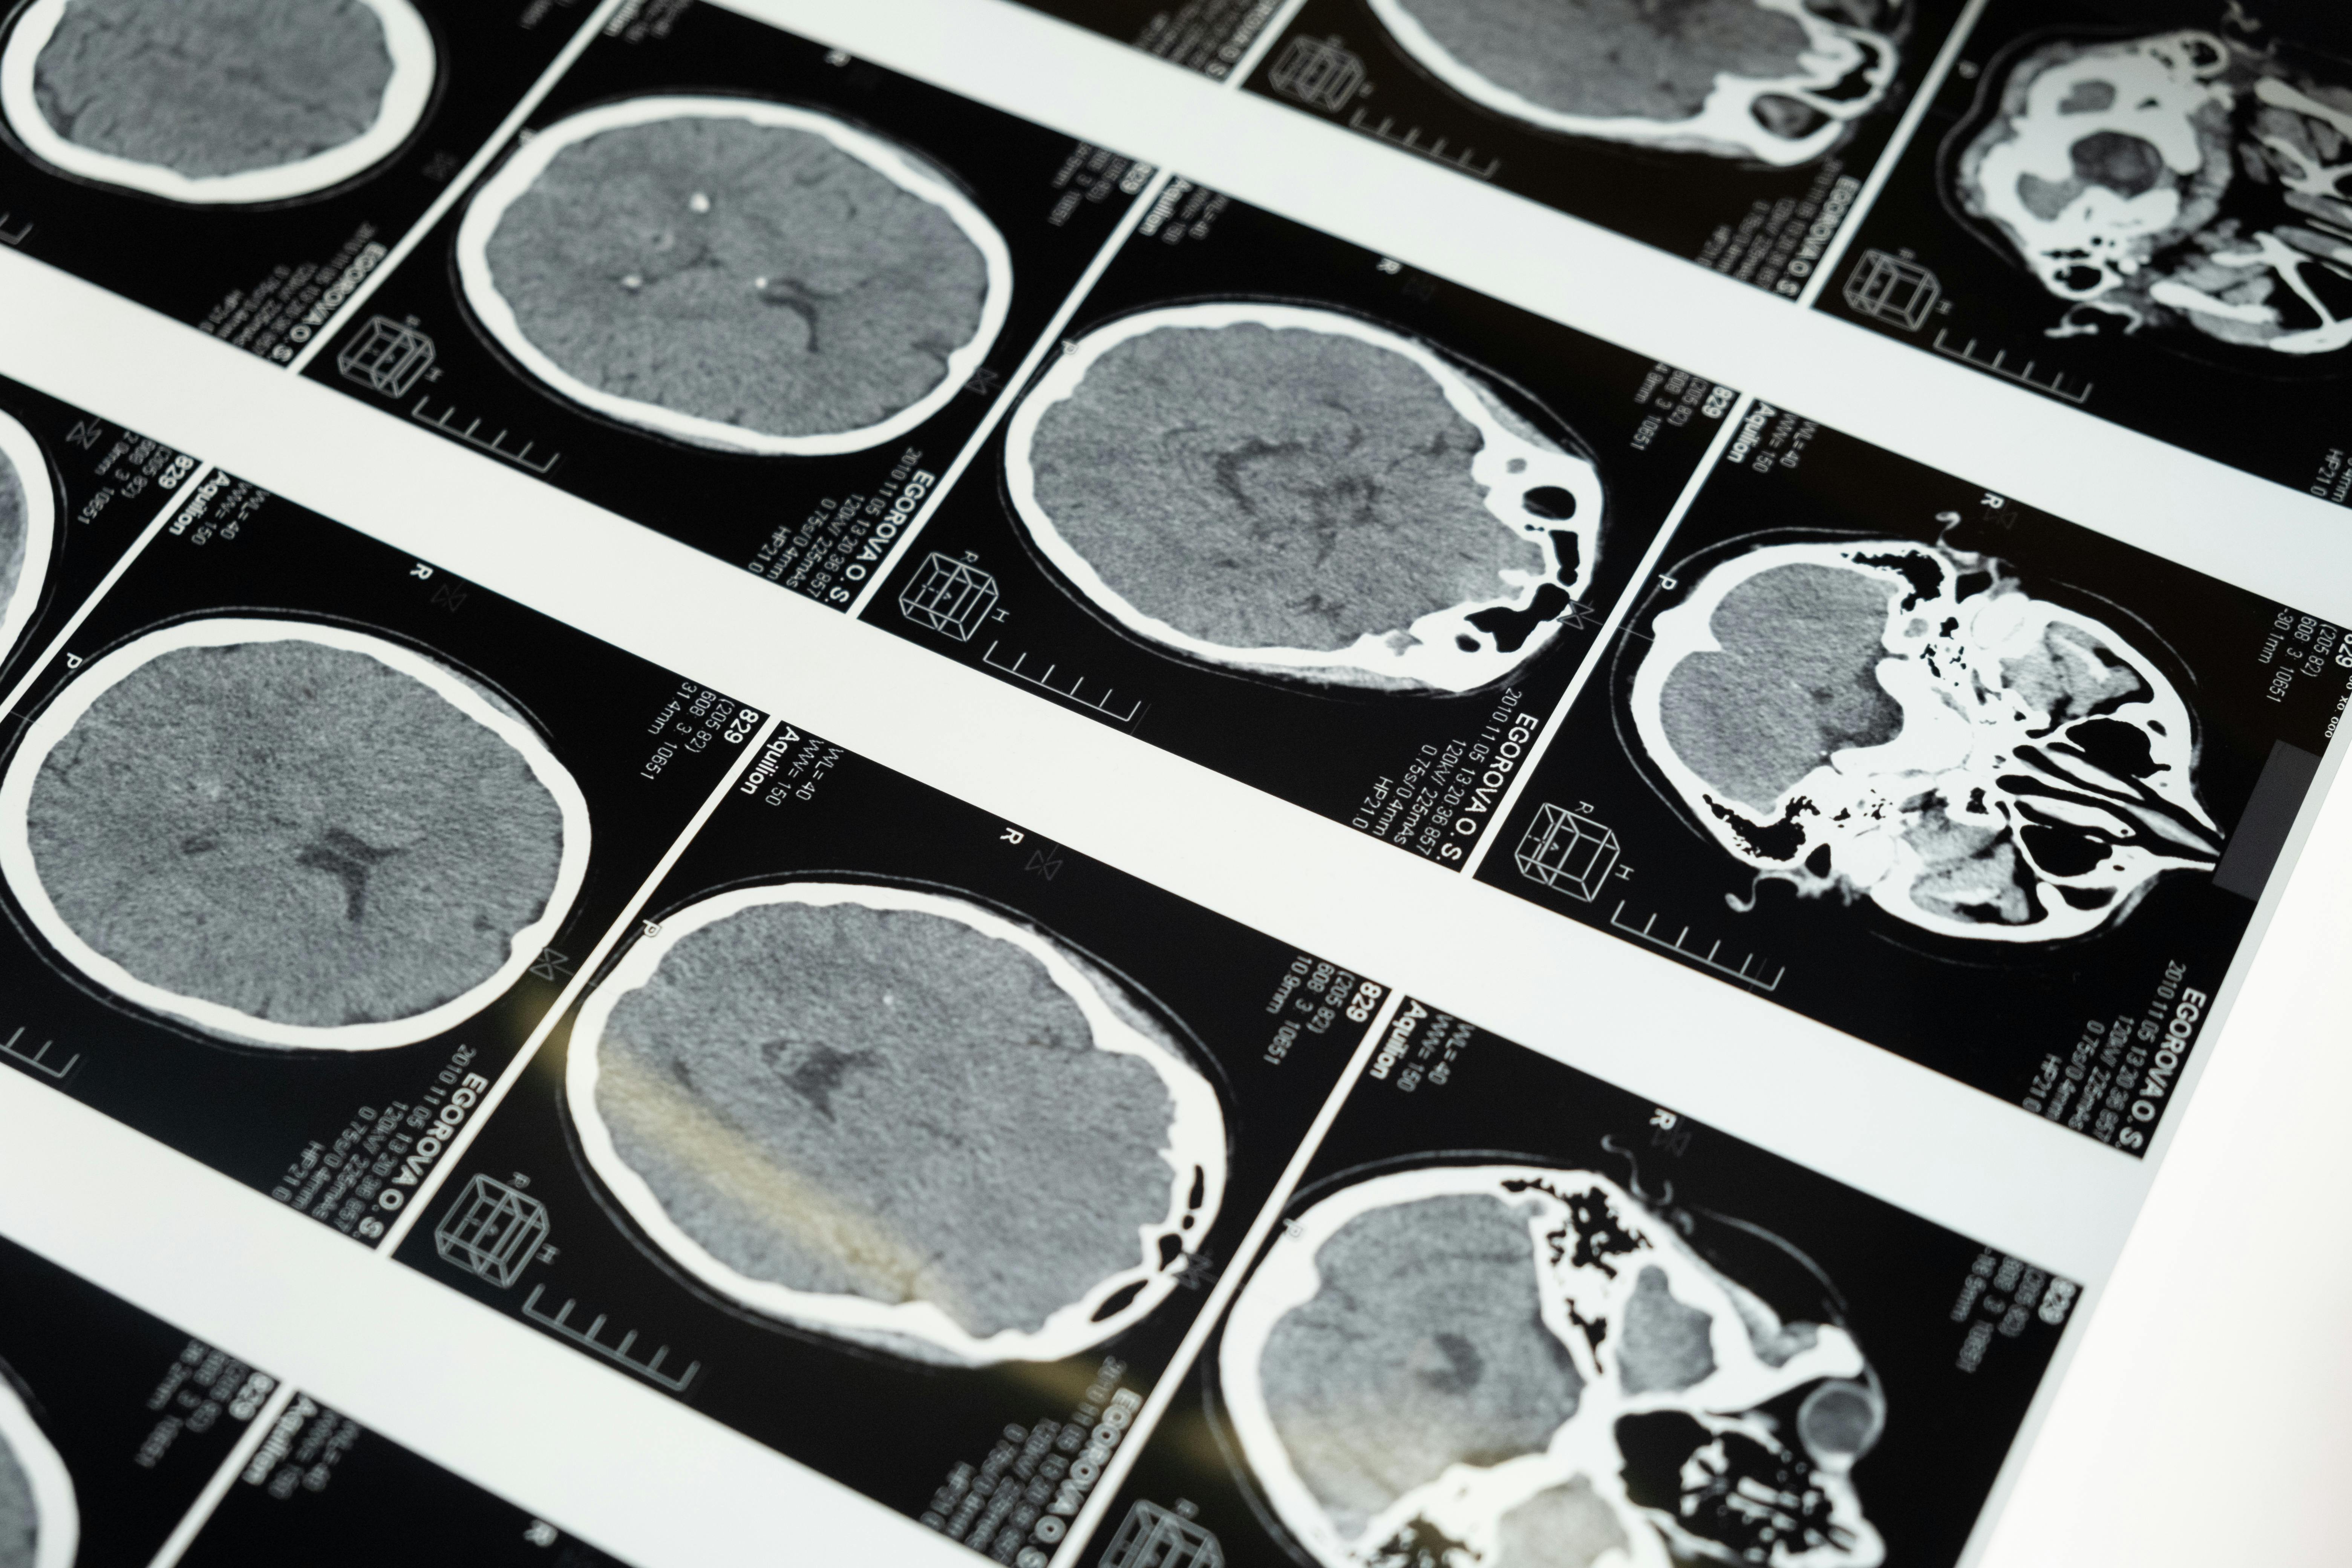

Přednáška představí klíčové objevy, které proměnily naše chápání nádorové imunity mozku, se zvláštním důrazem na imunosupresivní mikroprostředí mozkových nádorů a jeho vliv na průběh onemocnění. Pozornost bude věnována zejména glioblastomu, nejmalignějšímu nádoru mozku u dospělých, jehož imunitní mikroprostředí je předmětem intenzivního výzkumu vědců z 1. lékařské fakulty UK, kteří jsou součástí Národního ústavu pro výzkum rakoviny (NÚVR).